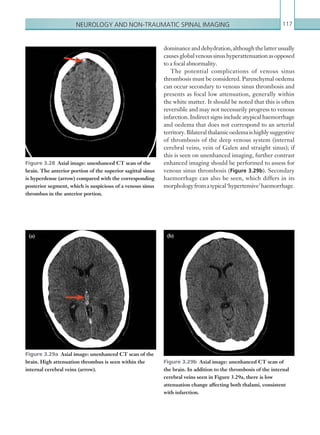

• 229.

STANDARDS OF PRACTICEAND GUIDANCE FOR TRAUMA RADIOLOGY 207 Standard 4. Digital radiography must be available in the emergency room. FAST Focusedabdominalsonographyintrauma(FAST)does not offer any additional information to that obtained with a CT scan and should not be performed if it would delay transfer to CT. FAST is a poor discriminator of therequirementorotherwiseforlaparotomyintrauma. Studies have shown negative predictive values of only 50–63% for FAST in unstable patients.7,8 FAST does have value in the diagnosis of pericardial effusion and in experienced hands might detect free intra-abdominal fluid in an otherwise non-compromised patient. It has an important role in triage when managing multiple SIPs simultaneously or in a major incident scenario. As with all imaging, a report on a FAST scan should be documented and the designation of the operator recorded. Standard 5. If there is an early decision to request MDCT, FAST and DR should not cause any delay. Magnetic resonance imaging (MRI) MRI is not indicated in the setting of acute trauma care. However, in the MTC, it must be available 24 hours a day, seven days a week. It should be in the same building as the emergency department or, if it is in a different building, protocols should be in place for the transfer of critically injured patients if further management is dependent on MRI in the first 12 hours. InaTUwithoutaccessto24-hourMRI,formalwritten protocols should be in place for the transfer of patients to a facility that has 24-hour MRI. Quality indicator WhereFASTorplainfilmshavebeenusedinaSIP, their use and value in that case should be evaluated in a multidisciplinary debriefing. Quality indicator An annual audit of justification in trauma imaging should be carried out by the radiology department. Standard 6. MRI must be available with safe access for the SIP. Indications for imaging in the SIP As stated above, there may be indications for plain DR but these should never delay an MDCT if a decision has been taken early that this is the imaging modality of choice. There may be circumstances where imaging is inappropriate;forexample,whereaSIPisadmittedwith profound shock, is not responding to intravenous fluids and the site of bleeding is clear from the mechanism of injury and rapid assessment. Such patients may be best taken straight to theatre. The more accessible the MDCTscanneristotheemergencyroomandthemore efficient CT transfer organisation is, the less frequently this should happen. A polytrauma protocol MDCT is indicated when: • There is haemodynamic instability. • The mechanism of injury or presentation suggests that there may be occult severe injuries that cannot be excluded by clinical examination or plain films. • FAST (if used) has demonstrated intra-abdominal fluid. • If plain films suggest significant injury, such as pneumothorax, pelvic fractures. • Obvious severe injury on clinical assessment. Standard 7. A CT request in the trauma setting should comply with the Ionising Radiation (Medical Exposure) Regulations 20009 (IR(ME)R) justification regulations like any other request for imaging involving ionising radiation. Quality indicator Availability of clear protocols for the transfer of SIPs to MRI facilities within 12 hours. K22247_Appendix II.indd 207 16/05/15 3:16 AM

• 230.

Appendix 2208 Appendix 1demonstrates a sample request card which trusts can modify according to local needs. NOTE: SomeMTCsinotherEuropeanandNorth American countries have adopted a ‘CT first’ protocol. The UK awaits the results of the Randomized study of Early Assessment by CT scanning in Trauma patients (REACT)trialcurrentlyrecruitingpatientstoaCT-first or resuscitation-first protocol in the Netherlands. The result of that study might supersede the indications above and major trauma itself may justify immediate MDCT 10 delaying only in the resuscitation area for time-critical interventions such as securing an airway or profound hypotension. Preparation and transfer to MDCT There should be agreed local protocols with clear attribution of responsibility for every stage. Request for MDCT Clear protocols must exist for notifying the CT department of the need for urgent imaging and how the department will respond to ensure that the scanner is clear to receive the incoming injured patient. It must be clear who is responsible for this at both ends. There should be a detailed polytrauma request form (see Appendix 1). Transfer route to CT This must be established in advance. Transfer staff should be notified well in advance. IV access Right antecubital access is preferred for contrast administration (left-sided injections compromise interpretation of mediastinal vasculature). However, if arm vein access is not possible and a central line is in situ, it should be of a type that can accept 4 ml contrast/ second via a power injector. This might require local negotiation with emergency department doctors beforehand. Pelvic fracture If a pelvic fracture is suspected, a temporary pelvic stabilisation (wrap, binder and so on) should be applied before MDCT. Limb fractures Rapid immobilisation such as air splints. Only immediately limb conserving manipulations/splinting should be performed prior to CT. Urinary catheter All significantly injured patients without obvious contraindications should be catheterised unless this would delay transfer to CT. The catheter should be clamped prior to MDCT. Pregnancy There must be awareness of pregnancy status in female SIPs of childbearing age. The health of the mother takes precedence over the health of the fetus and, if appropriate, modification of pathways should be decided by the trauma team leader and consultant radiologist. Standard 8. There should be clear written protocols for MDCT preparation and transfer to the scan room. MDCT imaging protocols Whole-body MDCT has been shown to be a predictor of survival in SIPs when compared to no CT or targeted CT.11 Clearly there are many abnormalities that might be detected on whole-body MDCT in the SIP and protocolsshouldbedesignedtoimagetheseasclearlyas possible. Protocols should be the same across networks so that repeat scanning is not required where transfer is necessary. Where active contrast extravasation is seen, the on-call interventional radiologist should be informed immediately along with the trauma team leader. Where findings are equivocal, the on-call consultant radiologist shouldbeaskedforanimmediate opinion. Quality indicator Such protocols should be written and available and the process should be a statutory evaluation at debriefing. K22247_Appendix II.indd 208 16/05/15 3:16 AM

• 231.

STANDARDS OF PRACTICEAND GUIDANCE FOR TRAUMA RADIOLOGY 209 Examples of polytrauma CT protocols are listed in Appendix 2. An MDCT protocol should be agreed across a trauma network to ensure consistency and obviate the need for repeat scanning if transfer is necessary. The NHS CAG document2 refers to the patient who is ‘stable enough to undergo MDCT’. The phrase used reflects the difficulty in being too prescriptive in giving guidance about the stability of a SIP and fitness for investigation. It can be argued that the greater the haemodynamic instability, the greater the requirement for accurate diagnosis to allow targeted surgery/intervention. In the perfect emergency room environment where all imaging is immediately co-located, there should only be a very small minority of patients who are too unstable for MDCT. Such patients would probably require open procedures in the emergency room environment. However, local circumstanceswillvaryandundoubtedlysuchdecisions have to be made at the time by the trauma team leader after consultation. Protocols for unstable patient transfer should take accountofunitgeographyandberehearsedtomaximise the proportion of patients who can access CT. Standard 9. Whole-body contrast- enhanced MDCT is the default imaging procedure of choice in the SIP. Imaging protocols should be clearly defined and uniform across a regional trauma network. Standard 10. Future planning and design of emergency rooms should concentrate on increasing the number of SIPs stable enough for MDCT and intervention. Reporting The initial MDCT should be attended by an appropriately trained on-call radiologist. Trainees Quality indicator Imaging and reporting protocols should be agreed across referral regions and written protocols must be available. should involve on-call consultant radiologists as soon as possible. Reporting follows the Advanced Trauma Life Support (ATLS)12 system in that there should be an initial primary survey followed by a secondary survey. Initial primary survey review The aim of this is to give an immediate indication of the major life-threatening injuries while active management continues. The initial images should be reviewedlookingforthoracicinjuriesthatmightimpair breathing, vascular injuries that might cause bleeding and neurological injuries that might cause disability if not treatedrapidly. AsuggestedCT primarysurveypro forma is provided in Appendix 3. Such a form should be filled in at the time, signed and dated. A copy should be handed to the trauma team leader and a duplicate scanned into the radiology information system (RIS). Theclinicalteamshouldfillintheircontactdetailsso thatwhenthefulltraumaproformareportiscompleted, all the necessary points of contact are available. Standard 11. The primary survey report should be issued immediately to the trauma team leader. It should be signed and designated and a copy should be retained in the CT department (or RIS). Secondary/definitive survey Once the initial scan results and pro forma have been communicated to the trauma team, the scan should be carefully reviewed against a written set of criteria and the secondary trauma report completed (Appendix 4). Thisshouldbeperformedbyaconsultantradiologistor in consultation with a consultant radiologist who may provide this report via a teleradiology link of suitable quality.13 NOTE: Radiologists working remotely for teleradiology companies have imaging equipment that allows diagnostic reports in real time and the UK military have reporting facilities in the UK that allows accurate reporting of trauma scans from field hospitals anywhere in the world, although they do deploy radiologists on site to cope with rapid fluctuations in patient care. All the areas listed in Appendix 4 should be reported on. This report should be completed within one hour to ensure there is no unnecessary delay to clinical K22247_Appendix II.indd 209 16/05/15 3:16 AM

• 232.

Appendix 2210 management. Anysignificant findings, particularly where there is a variance to the initial primary survey report, should be telephoned through to relevant clinicians. Again, the list of contact details will be invaluable where there is a change in findings.14 Standard 12. On-call consultant radiologists should provide the final report on the SIP within one hour of MDCT image acquisition. Standard 13. On-call consultant radiologists must have teleradiology facilities at home that allow accurate reports to be issued within one hour of MDCT image acquisition. Interventional radiology (IR) The role of IR in the SIP is to stop haemorrhage as quickly as possible with minimal interference to the patient’s already damaged physiology. It is as much a form of damage control as pressing on a bleeding artery or surgical packing. Information supplied by MDCT is key to informing the decision-making process and guiding a catheter to the haemorrhage site. It is likely that there will never be Level 1 evidence for endovascular techniques in trauma but, with this caveat, there are no significant contraindications to the use of IR to arrest haemorrhage in major trauma. There is a growing body of Level 2/3 evidence for its safety, efficacy, speed and cost-effectiveness. The decision on whether a patient with traumatic haemorrhage undergoes endovascular treatment, open surgery, a combination of the two or non-operative management (NOM) is typically a decision made by both the trauma team leader and the interventional radiologist after consultation with other consultants involved (Appendix 5). Decisions must be made quickly and should be driven by agreed algorithms. Establishing routes of communication between the services is paramount. Quality indicator All imaging should be discussed at debriefing meetings and errors of protocol or fact discussed at discrepancy meetings.15 A checklist of quality indicators for IR is provided in Appendix 6. Endovascular theatres When IR is indicated in SIP management, rapid access to endovascular intervention is essential. Therefore, angiography facilities should be located as close as possible to the emergency department and should certainly be in the same building and on the same floor. In future, angiography suites should be co-located within an acute theatre complex/emergency room that provides surgical and anaesthetic support to acutely ill patients. Such facilities are not yet available in the UK. Standard 14. IR facilities should be co-located to the emergency department. Facilities Angiography suites must have modern (installed within the last ten years) fixed C-arm imaging equipment. Roomsneedtobelargeenoughtohandlethenumerous individuals who accompany the very unstable trauma patient. They should have the same facilities as an operating theatre and ideally should have positive pressure air change. Portable C-arm equipment should only be used in the context of immediate stabilisation by occlusion balloon inflation. Portable units do not offer the same imaging quality as fixed units and there is evidence of patient harm occurring with the use of such units, principally due to poor image quality.16 In addition, portable units can only operate for a limited time before overheating. Standard 15. Angiographic facilities and endovascular theatres in MTCs should be safe environments for SIPs and should be of theatre standard. Protocols Local services should take particular care to develop transfer protocols for both internal and external anaesthetic supported transfer. A frequent source of delay in many centres is the internal transfer of haemodynamically compromised patients for CT imaging or embolisation. Agreed pathways and improvements to local environment should be K22247_Appendix II.indd 210 16/05/15 3:16 AM

• 233.